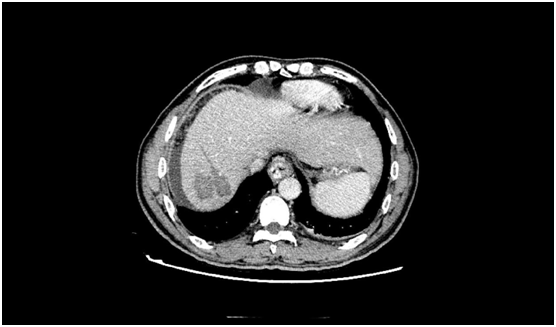

術(shù)前發(fā)現(xiàn)患者的肝臟5段有一個5.5cm大小的惡性腫瘤,此外還有大量腹水、門脈高壓癥、脾功能亢進(jìn),同時合并有消化道出血、肝功能差等癥狀。而在患者的肝臟7段,亦存在一個2cm大小的肝內(nèi)轉(zhuǎn)移灶。

術(shù)后復(fù)查CT見腫瘤全部失去了活性